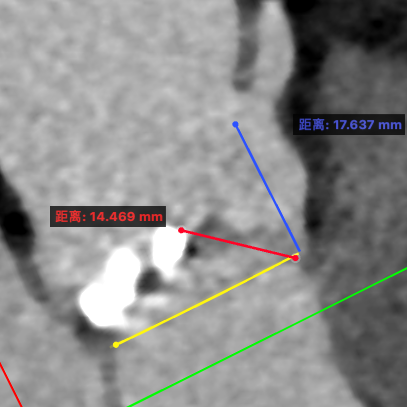

武汉协和董念国团队对该病例进行了缜密探讨,该病例为老年男性,主动脉瓣中重度狭窄,术前左室舒张功能减低。患者病例CT和心超数据显示瓣环周长:90.2mm,瓣下4mm流出道周长:97.5mm,窦部空间相对小,单纯无冠瓣瓣叶钙化,三叶瓣。左冠风险较高,缜密分析瓣叶遮盖率>50%,术中可能存在阻挡风险,需要术中球囊扩张时仔细辨认,并准备冠脉保护策略。综合评估考虑右股动脉更适宜为主入路。经过团队严谨的评估及充分的讨论,决定先行25mm球囊预扩并进一步确认冠脉风险,并准备TAV29和TAV32规格的ProStyle预装式可回收TAVR系统。

左冠评估

右冠评估

瓣环切线位窦部空间

左室空间

工作位1(共平面/左冠切)

工作位2(无窦切线/左右重叠)